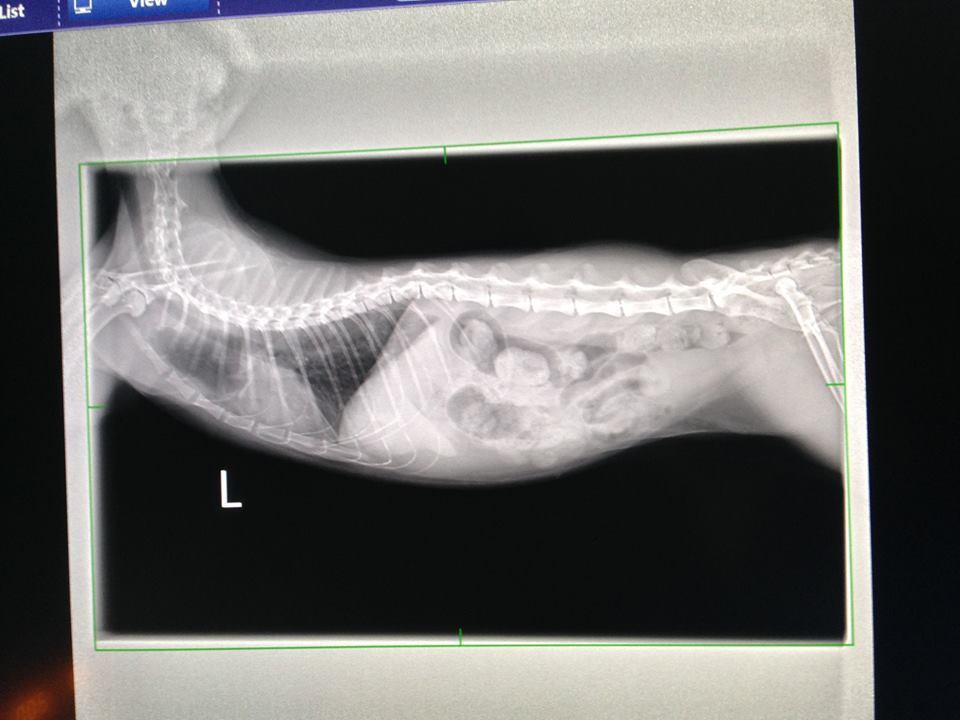

今日有拍X光查看肺部的團塊

肺部與上次相比有較為清澈

拍x光確認肺部的團塊已不如以往明顯

今日同樣有拍X光查看肺部的團塊

左肺跟之前相比乾淨非常多

但在右肺約第8.9根肋骨處從治療前就有個白色結點

現在仍是很明顯,但不確定是否已纖維化